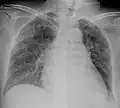

A case of miliary tuberculosis in an 82-year-old woman:

X-ray, 13 days after onset, showing bilateral interstitial infiltrates